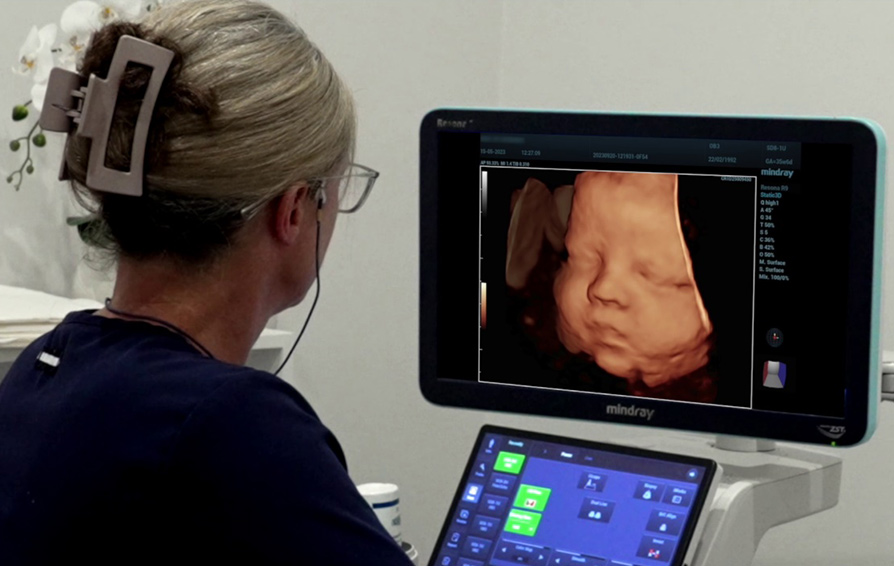

Narelle Woods, a seasoned sonographer at South Coast Ultrasound for Women, reflects on the incredible advancements she has witnessed in her 20 years of experience. Specializing in obstetrics and gynecology ultrasounds, Narelle describes the joy she finds in her work, particularly in the dynamic nature of the images produced by modern ultrasound machines. She notes that advancements in technology have allowed her team to detect complex abnormalities in fetal hearts, as well as early signs of conditions like breast cancer, at much earlier stages than ever before.

Dr. Glenn McNally, a partner at the ultrasound center, echoes Narelle's passion about the benefits of cutting-edge ultrasound systems, particularly the Mindray systems they have recently implemented. He praises the systems for their ease of use, intuitive interface, and exceptional image quality, which have enhanced the accuracy and confidence of their diagnoses.

Looking towards the future, Narelle emphasizes the enormous potential of ultrasound machines in women's imaging, highlighting their ability to rival traditional gold standard tests in quality and accuracy. From detecting conditions like endometriosis to improving healthy outcomes for babies, ultrasound technology plays a vital role in patient care and instills confidence in referring healthcare providers.

Mindray has always been dedicated in the advancements in ultrasound technology to revolutionize women's imaging and healthcare, enabling healthcare providers like Narelle and Glenn to deliver exceptional care and improved outcomes for their patients. As the field continues to evolve, the future of ultrasound holds limitless promise in providing accurate diagnoses and personalized care for women's health.